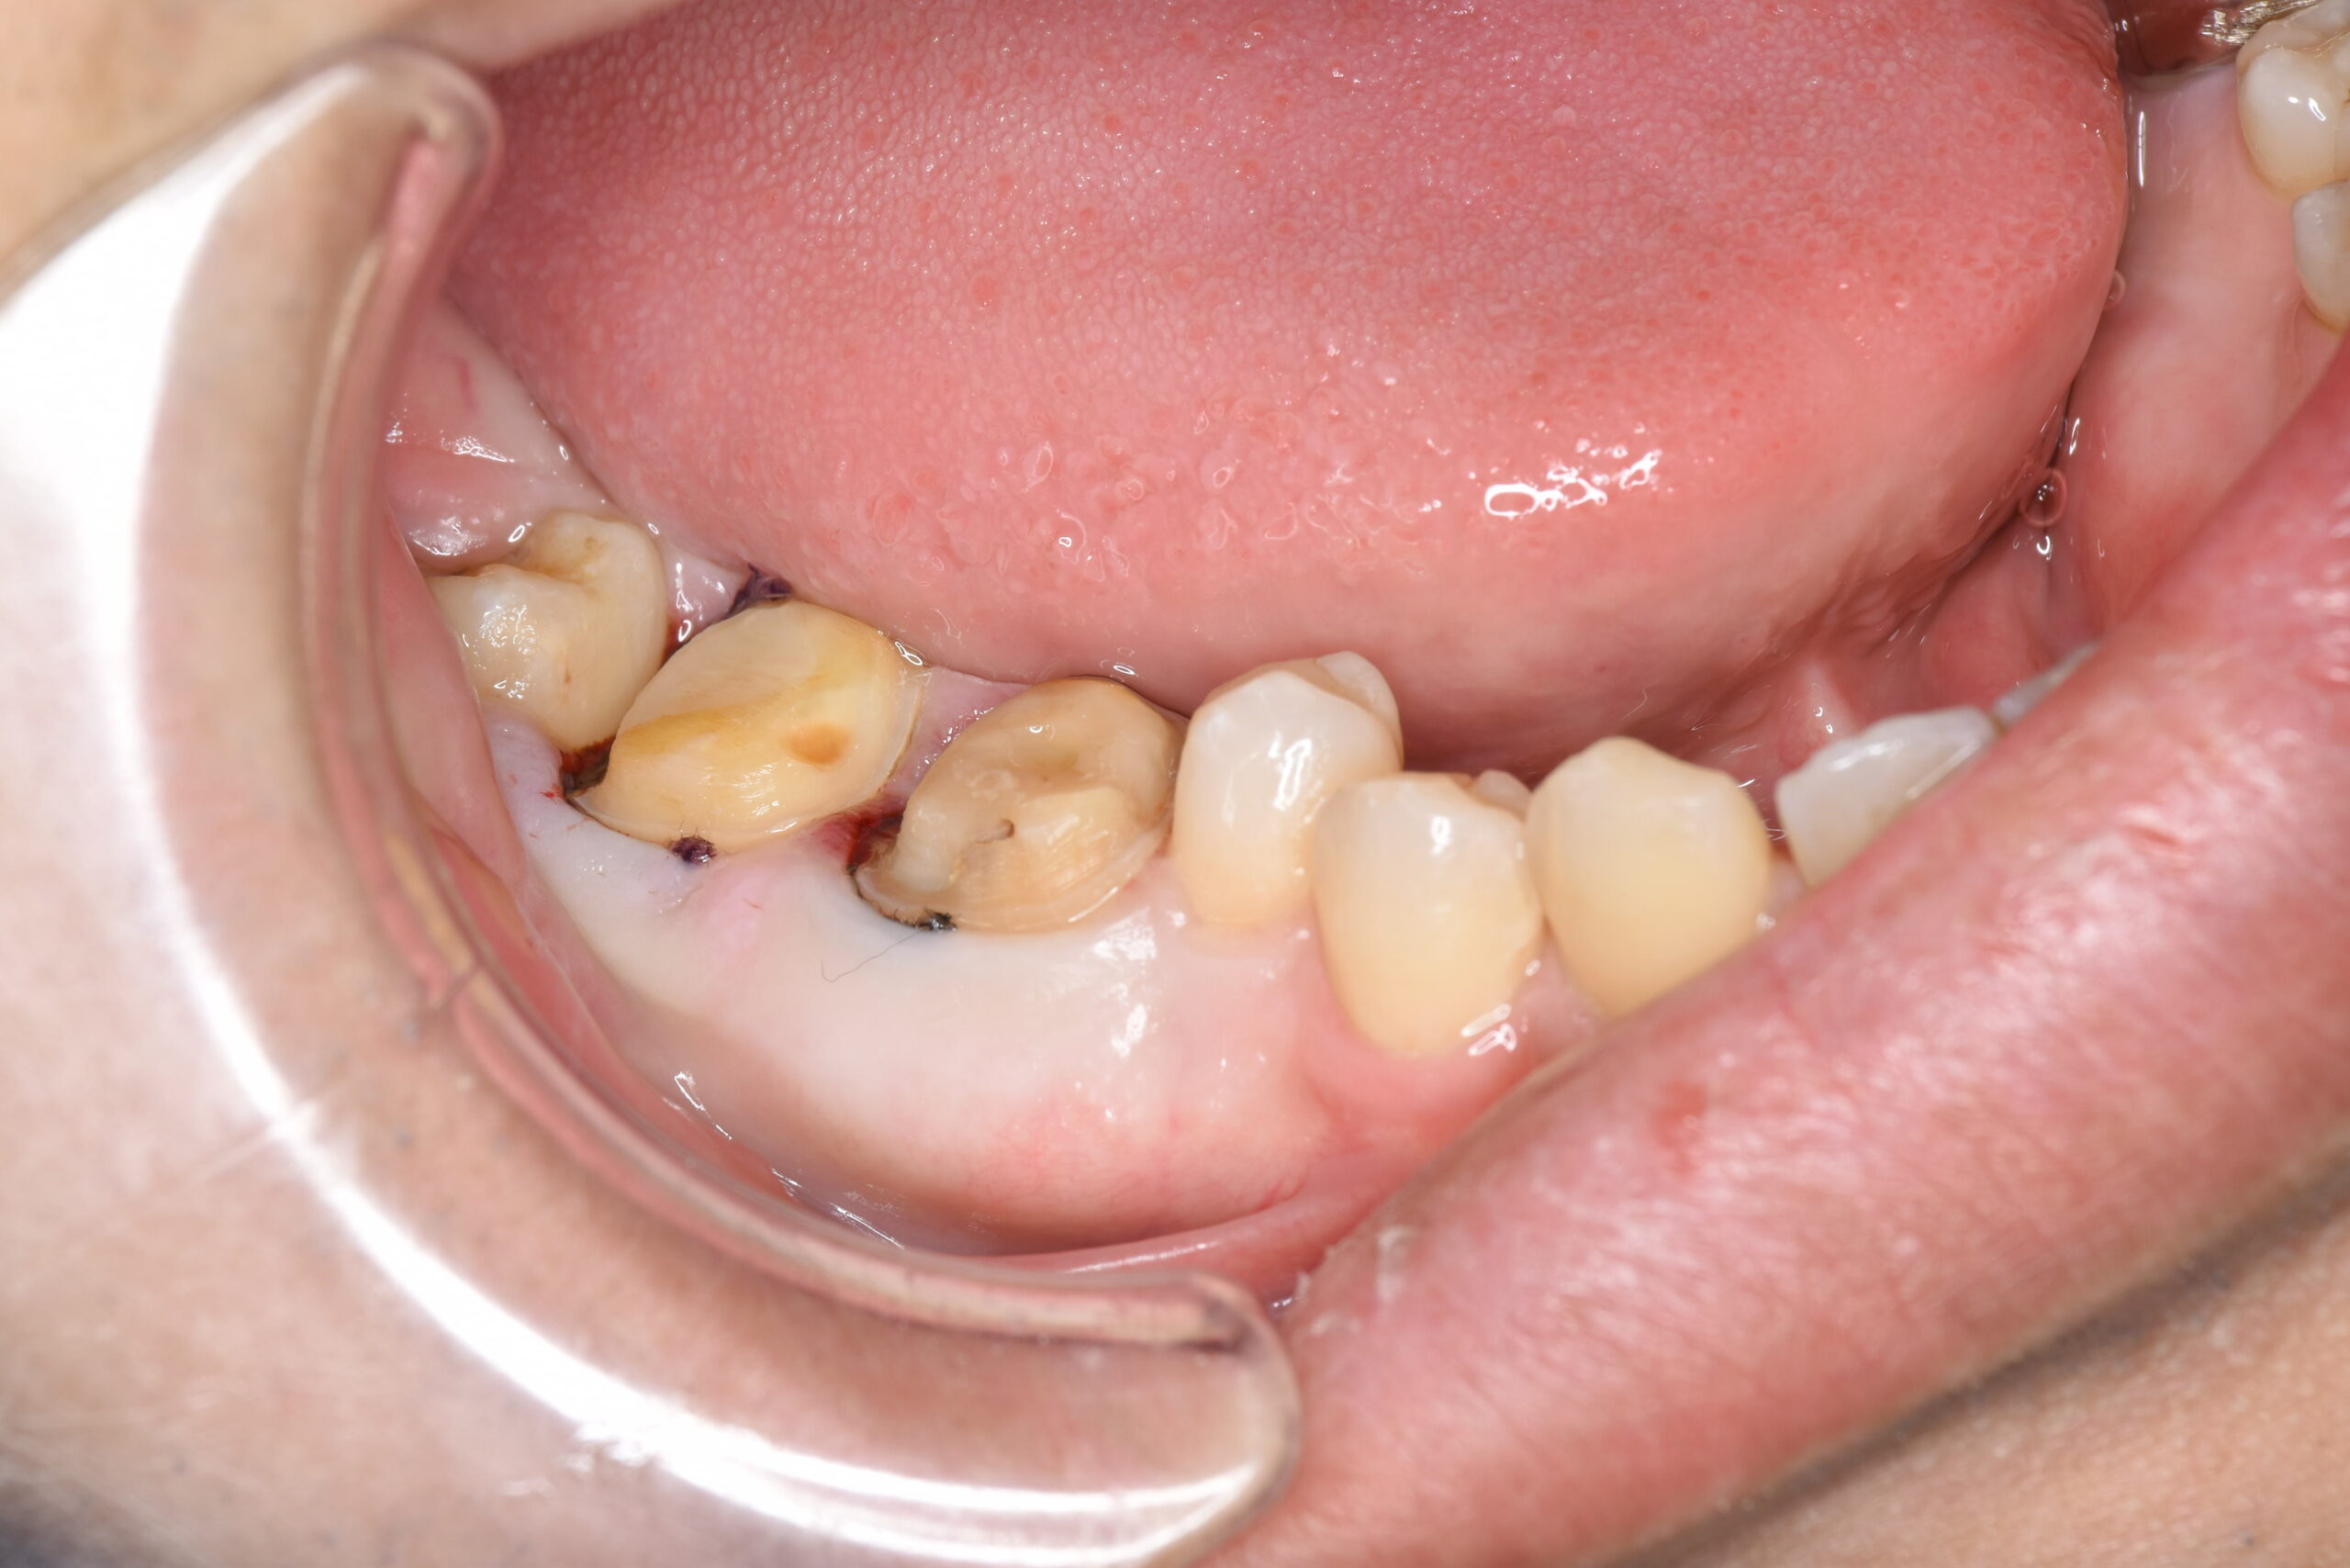

奥歯の痛みを主訴に来院されました。レントゲン検査にて奥歯に大きな虫歯が見つかり、神経が保存できる状態ではありませんでした。ご本人様は、歯を積極的に残したいとのことでしたので、専門医での神経治療をご提案しました。

歯内療法専門医での根管治療終了後、当院にてセラミックによる被せ物治療を行いました。